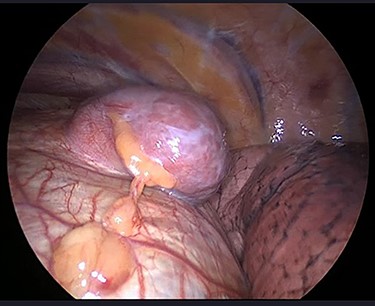

The operation was performed under general anaesthesia with the patient intubated using a double-lumen endotracheal tube. A 4 cm incision was made in the right sixth intercostal space in order to locate the mass. After the insertion of a 10 mm 30-degree thoracoscope, a rounded smooth-surfaced, broad necked mass attached to the right hemidiaphragm was visualized (Fig. 3). The decision to open the diaphragm was made. Further dissection and exploration with an energy device revealed that the mass which was bounded superiorly in the form of a pouch by the diaphragm and had arisen from the liver (Fig. 4). The mass was completely resected with HARMONIC ACE® +7 (Ethicon) after consulting with the hepatobiliary surgeon who felt there was a clear cleavage plane between the mass and liver. The exposed area of liver was covered with Floseal®(Baxter) and TachoSil®(Takeda). The diaphragmatic defect (Fig. 5) was closed in a single layer with 10 simple interrupted silk sutures (Fig. 6). The remainder of the surgery was uncomplicated, and the patient was discharged home on the second postoperative day. Subsequent histology findings reported the mass as benign (accessory) hepatic tissue (Fig. 7).